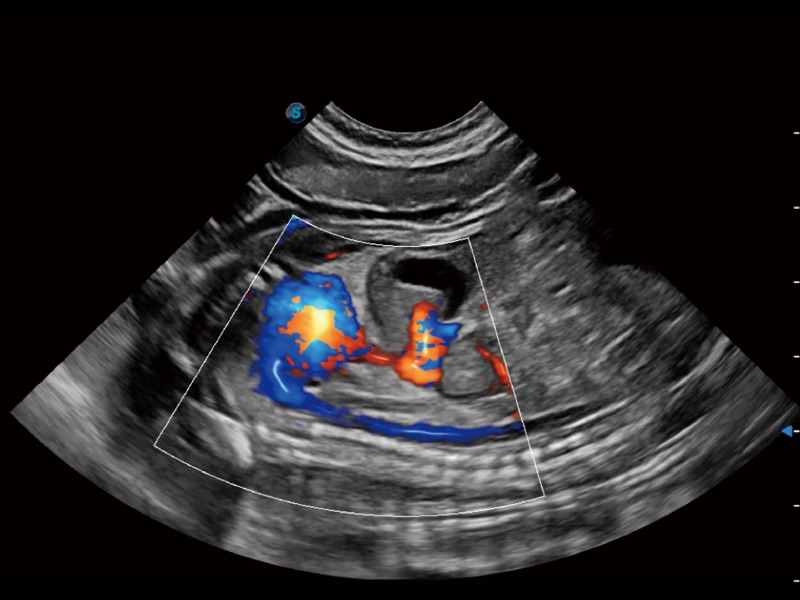

采用红、橙、黄、绿、青、蓝、紫这七种肉眼最为敏感的色彩,直观地显示组织内血流灌注的时间先后信息,更精准捕捉血流灌注走行细节。

实时用颜色表示心肌组织运动,观察和定量组织的运动情况,对快速检测与评估心肌的灌注和活性、电传导及心肌收缩和舒张功能等均能提供重要的诊断信息。